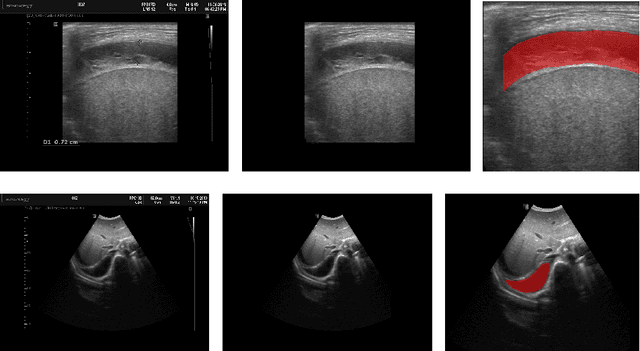

Abstract:In many low-to-middle income (LMIC) countries, ultrasound is used for assessment of pleural effusion. Typically, the extent of the effusion is manually measured by a sonographer, leading to significant intra-/inter-observer variability. In this work, we investigate the use of deep learning (DL) to automate the process of pleural effusion segmentation from ultrasound images. On two datasets acquired in a LMIC setting, we achieve median Dice Similarity Coefficients (DSCs) of 0.82 and 0.74 respectively using the nnU-net DL model. We also investigate the use of coordinate convolutions in the DL model and find that this results in a statistically significant improvement in the median DSC on the first dataset to 0.85, with no significant change on the second dataset. This work showcases, for the first time, the potential of DL in automating the process of effusion assessment from ultrasound in LMIC settings where there is often a lack of experienced radiologists to perform such tasks.